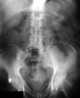

Nonvisceral abdominal calcification